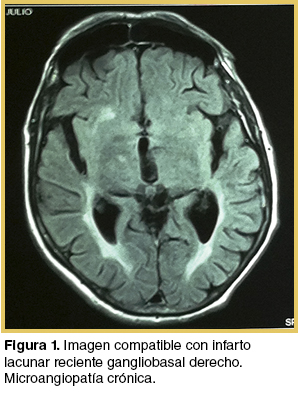

Con planteo de hemicorea de probable etiología vascular dada la instalación brusca de los síntomas, se solicita resonancia magnética (RM) de cráneo que muestra una imagen puntiforme a nivel gangliobasal derecho compatible con un infarto lacunar reciente, infartos lacunares gangliobasales contralaterales y microangiopatìa crónica (Figura 1).

En la hemicorea vascular la RM tiene mayor sensibilidad que la tomografía computada (TC) para demostrar la presencia de lesiones responsables. Estas se encuentran con mayor frecuencia en el tálamo y núcleo lenticular y, menos frecuentemente, en el núcleo subtalámico.(1)